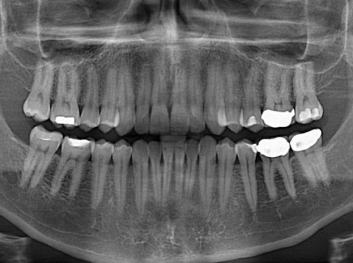

哈佛大學(xué):新型生物材料讓牙齒再生

損壞的牙齒如何自我修復(fù)?近日,來(lái)自哈佛大學(xué)和諾丁漢大學(xué)的研究人員研發(fā)了能夠刺激牙齒干細(xì)胞再生的新型生物材料,而這種新材料…